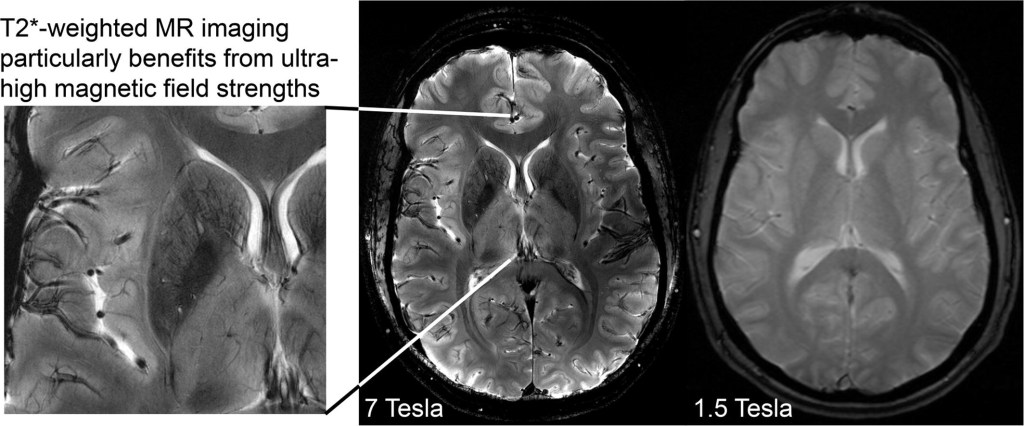

I am going to write all about the injury my daughter is suffering and the frequent episodes and constant rapid tranquilisations Castle Ward are giving on virtually a daily basis. I now want all the scans re-looked at as nothing can be relied upon under Lincolnshire who only have a 1.5 scanner. In my previous blogs I have included some interesting research papers on 1.5 MRI as opposed to Tesla 3. A Tesla 3 is why the private scans I had done revealed details not visible on a 1.5 scanner and I am warning everyone to check on which scanner their Trust has.

Chronic benzodiazepine use, such as repeated PRN rapid tranquillisation may be associated with alterations in brain structure and function. These changes may include reductions in grey matter volume, alterations in neurotransmitter systems, and neuroplastic changes.  Neuroplastic changes will show up on a 3 Tesla MRI scanner.  Presumably that is why certain people might not want such a scan done.

Neuroplastic changes can be detected using a 3 Tesla magnetic resonance imaging (MRI) scanner. A 3 Tesla MRI scanner is a powerful imaging tool that provides high-resolution images of the brain and has become the standard in clinical and research settings for studying brain structure and function.

A high resolution scan will indicate inflammation in the meso-limbic pathway affecting the dopamine receptors.  The 1.5 Tesla scanner does not have sufficient resolution to do this. Inflammation can cause psychomotor problems as well as psychotic symptoms.  Perhaps if they took the time to look for this specific adverse reaction they might not conclude the rather odd idea that the scan is normal.

I have already revealed Elizabeth’s scans which were done in November at Lincoln County Hospital with the result of “normal”. I would urge all of my readers to double check what scanner has been used as a 1.5 scanner has not picked up what is clearly visible on the private scans I had done through S G Radiology. I am waiting for an explanation as to what the images portray as I cannot accept these images to be normal. They even state “trauma” so as a parent or carer it is evident that you cannot always assume that normal means normal. A while back Elizabeth had an ultrasound as there were fears of cancer. Now I want all the scans done again under a Tesla 3. I have heard a Tesla 7 is even better and will look into where this can be done in the UK. So Lincolnshire, Enfield, Weston are just three examples where they do not have the up to date scanner and therefore you cannot rely on the results. This affects not just people under MH but everyone.

For so long now I have been trying to get answers – it clearly states “Anterior Region Medial Temperol Compromise which is not a mental illness and yet Elizabeth has been treated under MH with massive dosage of antipsychotics that do not work and is “treatment resistant” – poor/non metaboliser which I have prove by P450 tests. Now everything is falling into place and it is something I want to share with all of you especially those going through cancer treatment. Never trust the word “normal” and check what scanner your Trust has. I am currently asking my MP, Victoria Atkins why Lincolnshire does not have a scanner that is reliable. This means all of Elizabeth’s treatment may be affected as last year there was a cancer scare. Now I want all the scans/ultrasounds done through Sheffield and for Elizabeth to be referred to a Neurological Ward where for once her physical health can be properly assessed over a period of weeks. If the MH team stand in my daughter’s way of her physical health appointments and pathological tests I will report everything on here. I have already requested reports from all the professional bodies who have done nothing so far to stop the abuse to my daughter. Most importantly doctors should put the physical health of their patients first and foremost. I have now highlighted how patients are being deprived under just one area and how patients could have lost their lives due to the scans and how patients under the MH are refused pathological tests. This is why I was banned for months on end visiting my daughter and bullied by various doctors and this needs to be looked into. Police time has been wasted. Having lost close friends to cancer I intend to give this massive publicity.